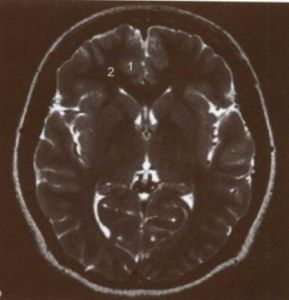

(1) 聯絡纖維:連結同側大腦半球。 (2)連合纖維:即胼胝體。 (3) 投射纖維:主要是內囊。 內囊:位於背側丘腦、尾狀核、豆狀核之間,由上行的感覺纖維和下行的運動纖維構成。在腦的水平切面上呈“><”狀,分為內囊前肢、內囊膝、內囊後肢三部。 1)內囊前肢:位於背側丘腦與尾狀核頭部之間。 2)內囊後肢:位於背側丘腦與豆狀核之間。主要有皮質脊髓束、脊髓丘腦束、視輻射等纖維束通過。 3)內囊膝:位於內囊前肢和內囊後肢交匯處,有 皮質核束通過。

圖大內囊內囊

a: 位置:位於尾狀核、豆狀核和背側丘腦之間。在大腦半球的水平切面上呈“>